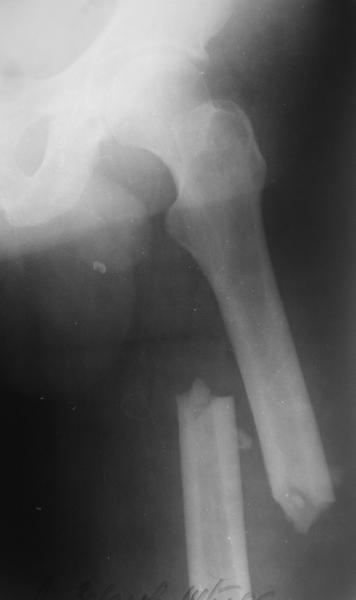

Изначально была выбрана не правильная точка введения стержня, в связи с чем в конце, я подчеркну, в конце операции произошло из-за напряжения между прокимальным концом канала бедра и стержнем разрушение в/3 бедра.

Проволока наложена потому, что при введении штифта не прошли эту зону римером и произошли сколы на концах отломков.

Под ЭОП во время операции такого смещения не было. Мы бы конечно не отпустили этого больного с такой картиной (сами бы что-то сделали или к вам отпр).

Зона раскола во время моей ревизии проходит по боковой поверхности как раз в зоне введения шеечного винта (картина как топор разрубил полено на две равных части, можа сделать КТ?)